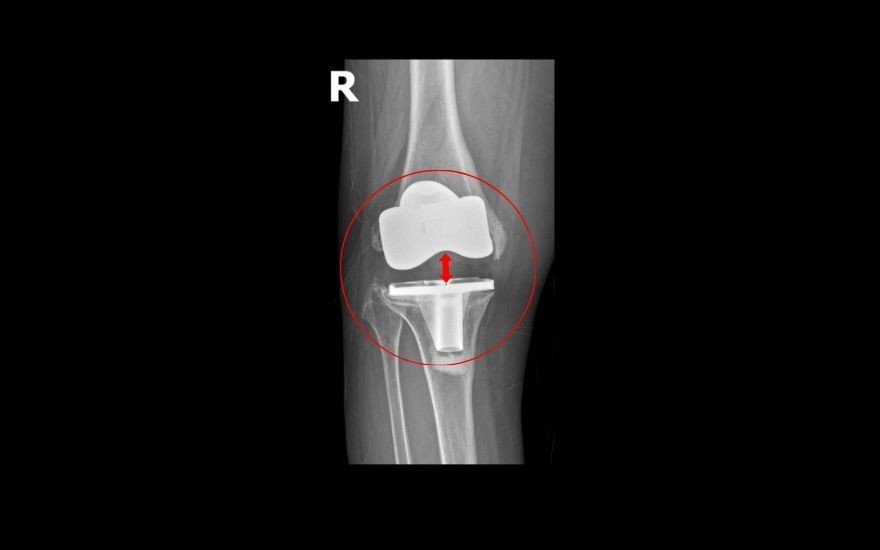

Theo TS.BS Lê Quang Huy, Trưởng khoa Ngoại Chấn thương chỉnh hình - Thần kinh sọ não, BVĐK Hồng Ngọc - Phúc Trường Minh: “Trường hợp của bệnh nhân Oanh hiếm gặp. Chỉ sau gần 5 năm phẫu thuật, cấu phần lồi cầu đùi nhân tạo (phần kim loại bao bọc đầu dưới xương đùi) đã lún vào lồi cầu trong xương đùi ~ 2cm, khiến khớp gối lệch khỏi vị trí ban đầu, mất vững kèm mất cân bằng mô mềm quanh khớp dẫn đến bệnh nhân không đi lại được. Các nguyên nhân gây biến chứng như nhiễm trùng hay viêm xương tuỷ đã được chúng tôi loại trừ, có thể do cơ địa bệnh nhân không phù hợp với loại khớp cấy ghép, tình trạng loãng xương nặng gây tiêu xương hoặc kỹ thuật cắt xương chưa thực sự chuẩn xác. Giải pháp duy nhất để phục hồi vận động và ngăn ngừa nguy cơ tàn phế là phẫu thuật thay lại khớp gối”.

Ca mổ của bà Oanh được đánh giá là phức tạp do gân cơ, dây chằng và cấu trúc xương quanh khớp tổn hại nghiêm trọng, đòi hỏi bác sĩ tính toán kỹ lưỡng để vừa khôi phục trục chân nguyên bản, vừa bảo tồn tối đa gân cơ, hạn chế biến chứng tái phát. Sau khi hội chẩn cùng GS. Hiranaka Takafumi (Giám đốc Trung tâm Phẫu thuật Khớp, Bệnh viện Takatsuki, Nhật Bản), TS.BS Lê Quang Huy quyết định loại bỏ khớp nhân tạo cũ, thay thế khớp mới bằng kỹ thuật thay khớp gối gióng trục động học, không cắt gân cơ với đường mổ nhỏ, ít xâm lấn, giúp bệnh nhân ít đau, có thể đi lại sau 1-2 ngày. Ngoài ra, bác sĩ sử dụng khớp bản lề chuôi dài để tăng độ vững, khôi phục trục chân, giúp người bệnh khôi phục chức năng và tầm vận động, hạn chế nguy cơ di lệch khớp.

Sau 2 giờ, ca mổ diễn ra thuận lợi. Khớp gối mới vừa vặn với ổ khớp, trục chân nguyên bản được khôi phục. Bà Oanh chia sẻ: “Lần mổ này nhẹ nhàng hơn lần mổ trước của tôi, lần trước, hơn 10 ngày tôi vẫn đau, không đi lại được. Lần mổ này, sau 2 ngày tôi đã vận động nhẹ nhàng, ngày thứ 5 tôi đã đi bỏ khung, tự chủ trong sinh hoạt cá nhân rồi. Tôi và gia đình đều bất ngờ bởi chỉ sau 1 cuộc phẫu thuật, tôi đã có thể đi lại được bình thường. Tôi xin gửi lời cảm ơn tới BS Huy cũng như tập thể nhân viên bệnh viện đã chăm sóc cho tôi rất chu đáo, tận tình.”